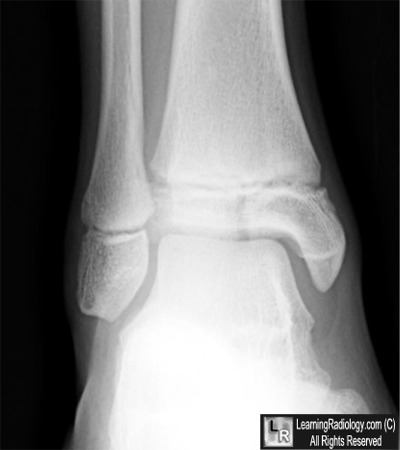

Case of the Week 518

What is the most likely diagnosis?

• 10 year-old with pain in ankle

Frontal radiograph of ankle

3. Salter-Harris Type III Fracture

Salter-Harris Fractures

• The epiphyseal plate (physis or growth plate) is the weakest part of the bone to shearing injuries

• The Salter-Harris classification is a means of categorizing epiphyseal plate fractures and provides clues to their prognosis

• All such these fractures, by definition, involve or extend through the epiphyseal plate so that all such fractures occur in children before the epiphyseal plate closes